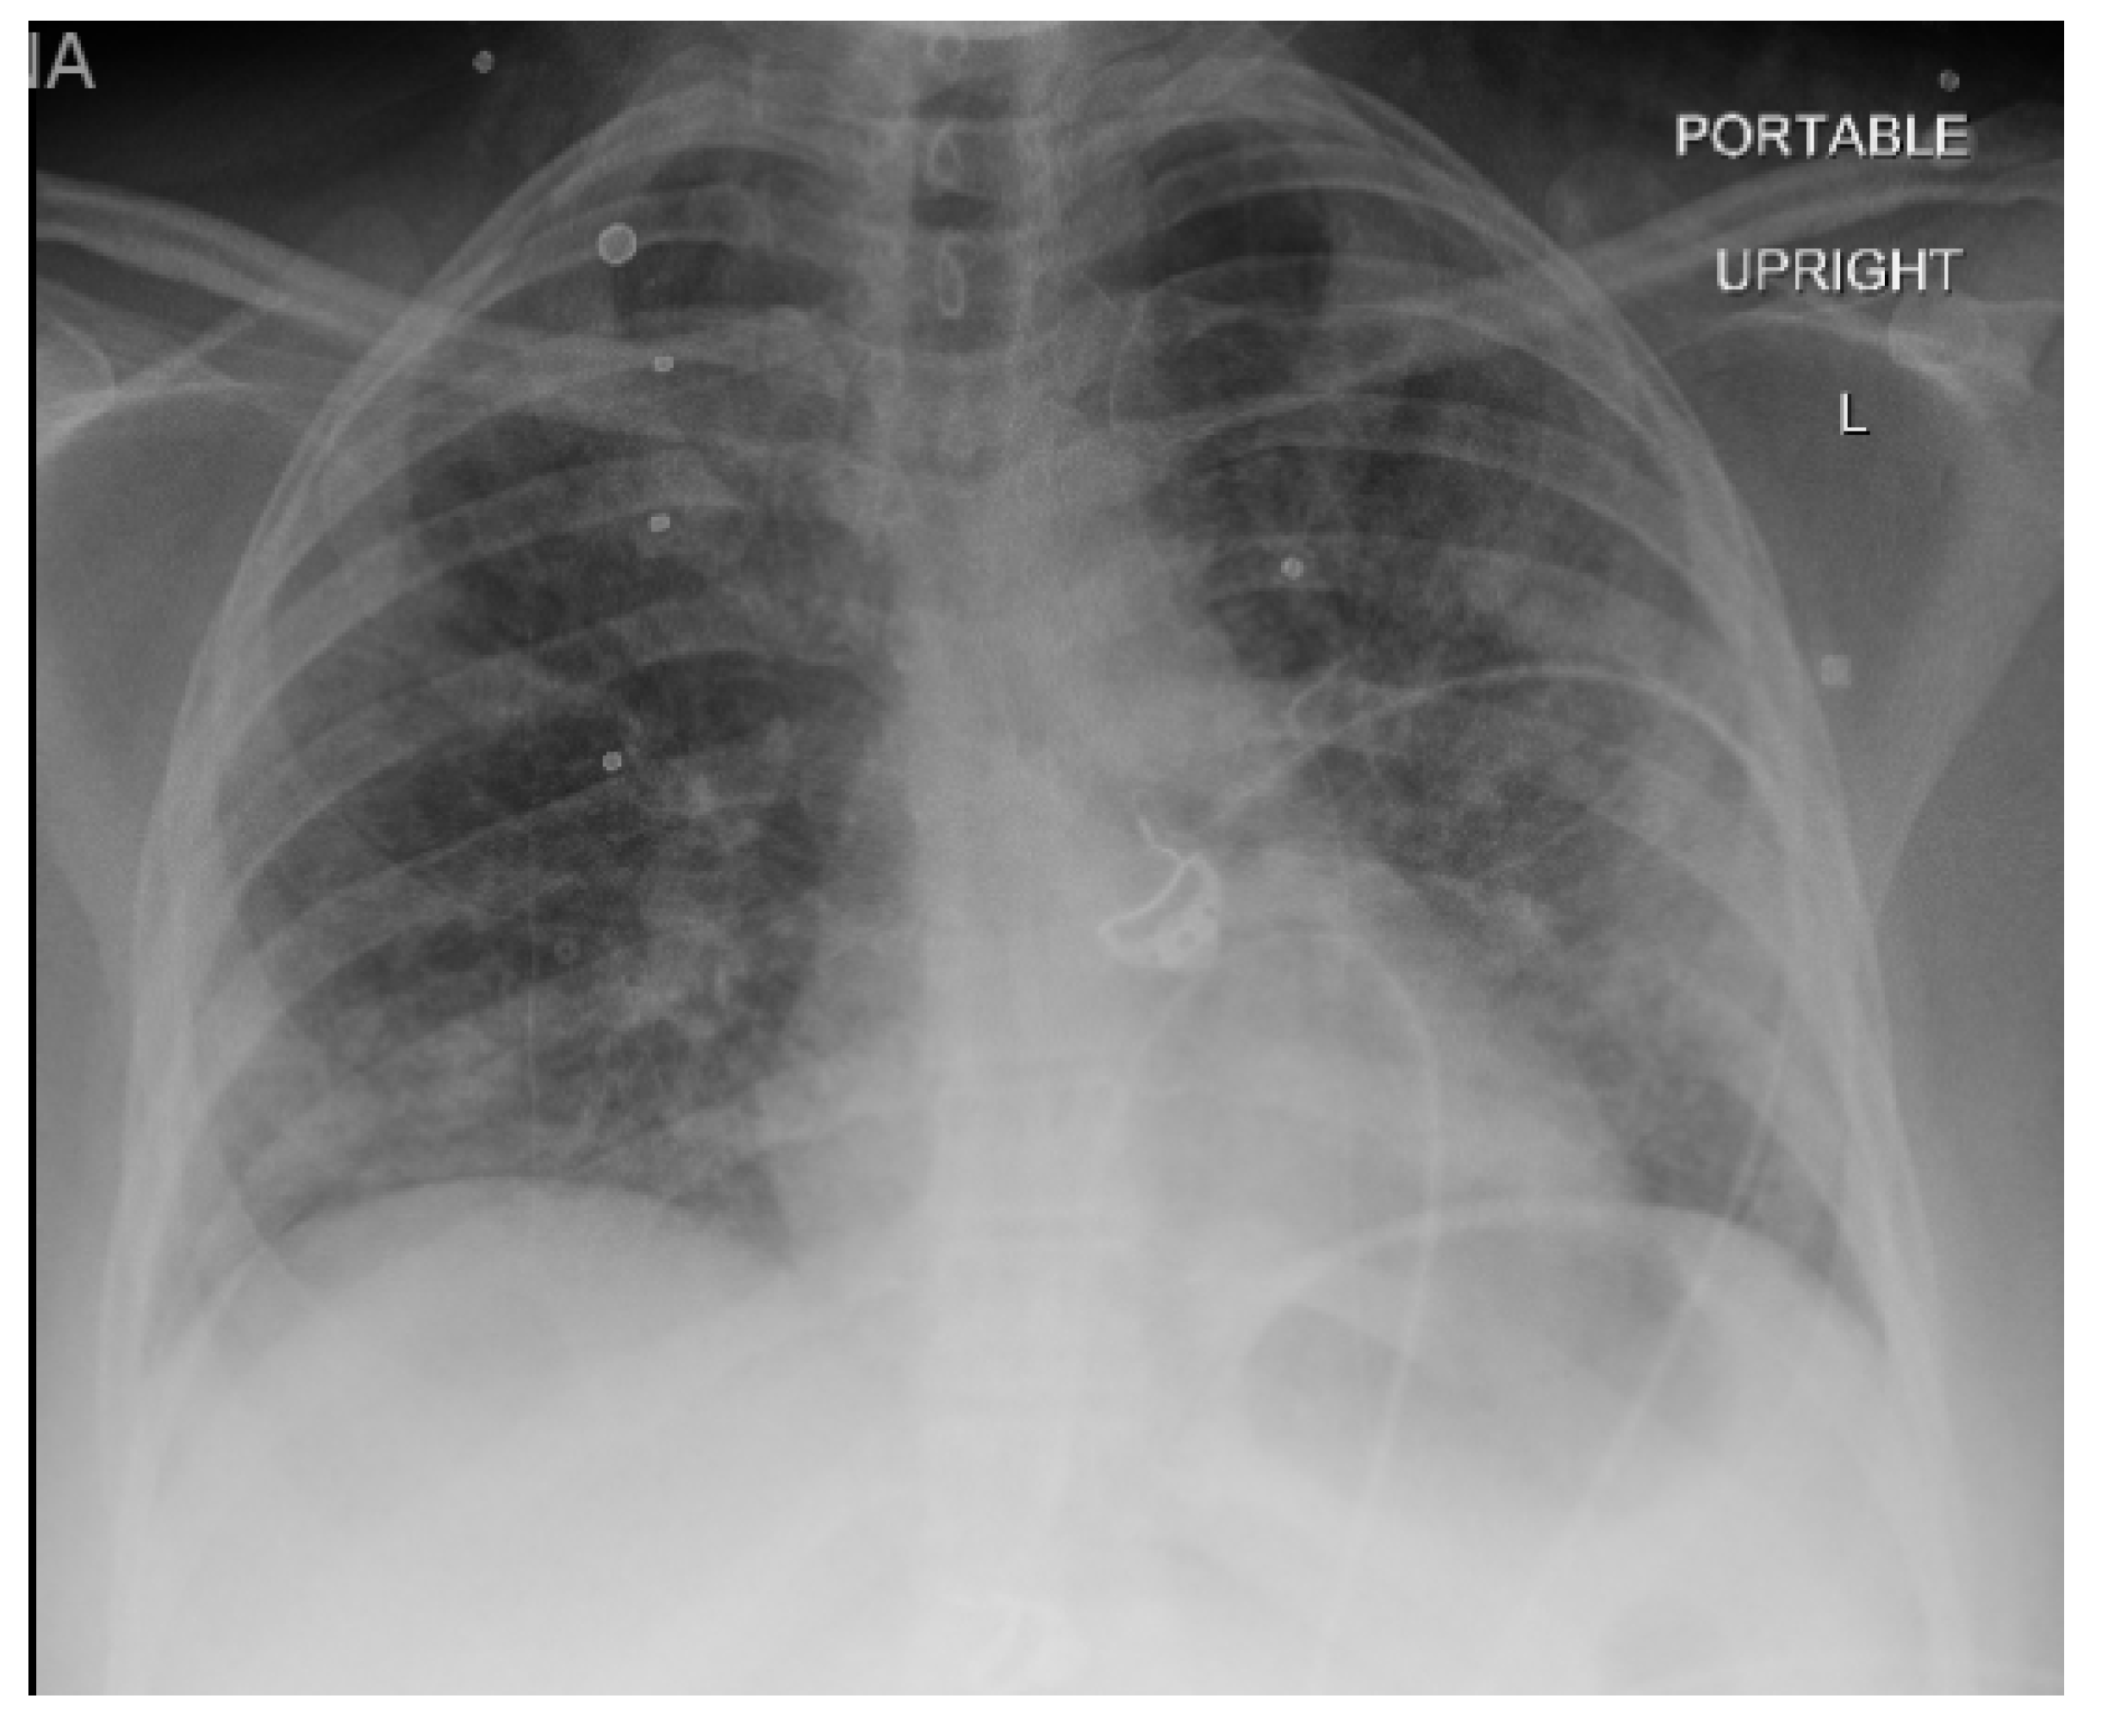

2. Case Report